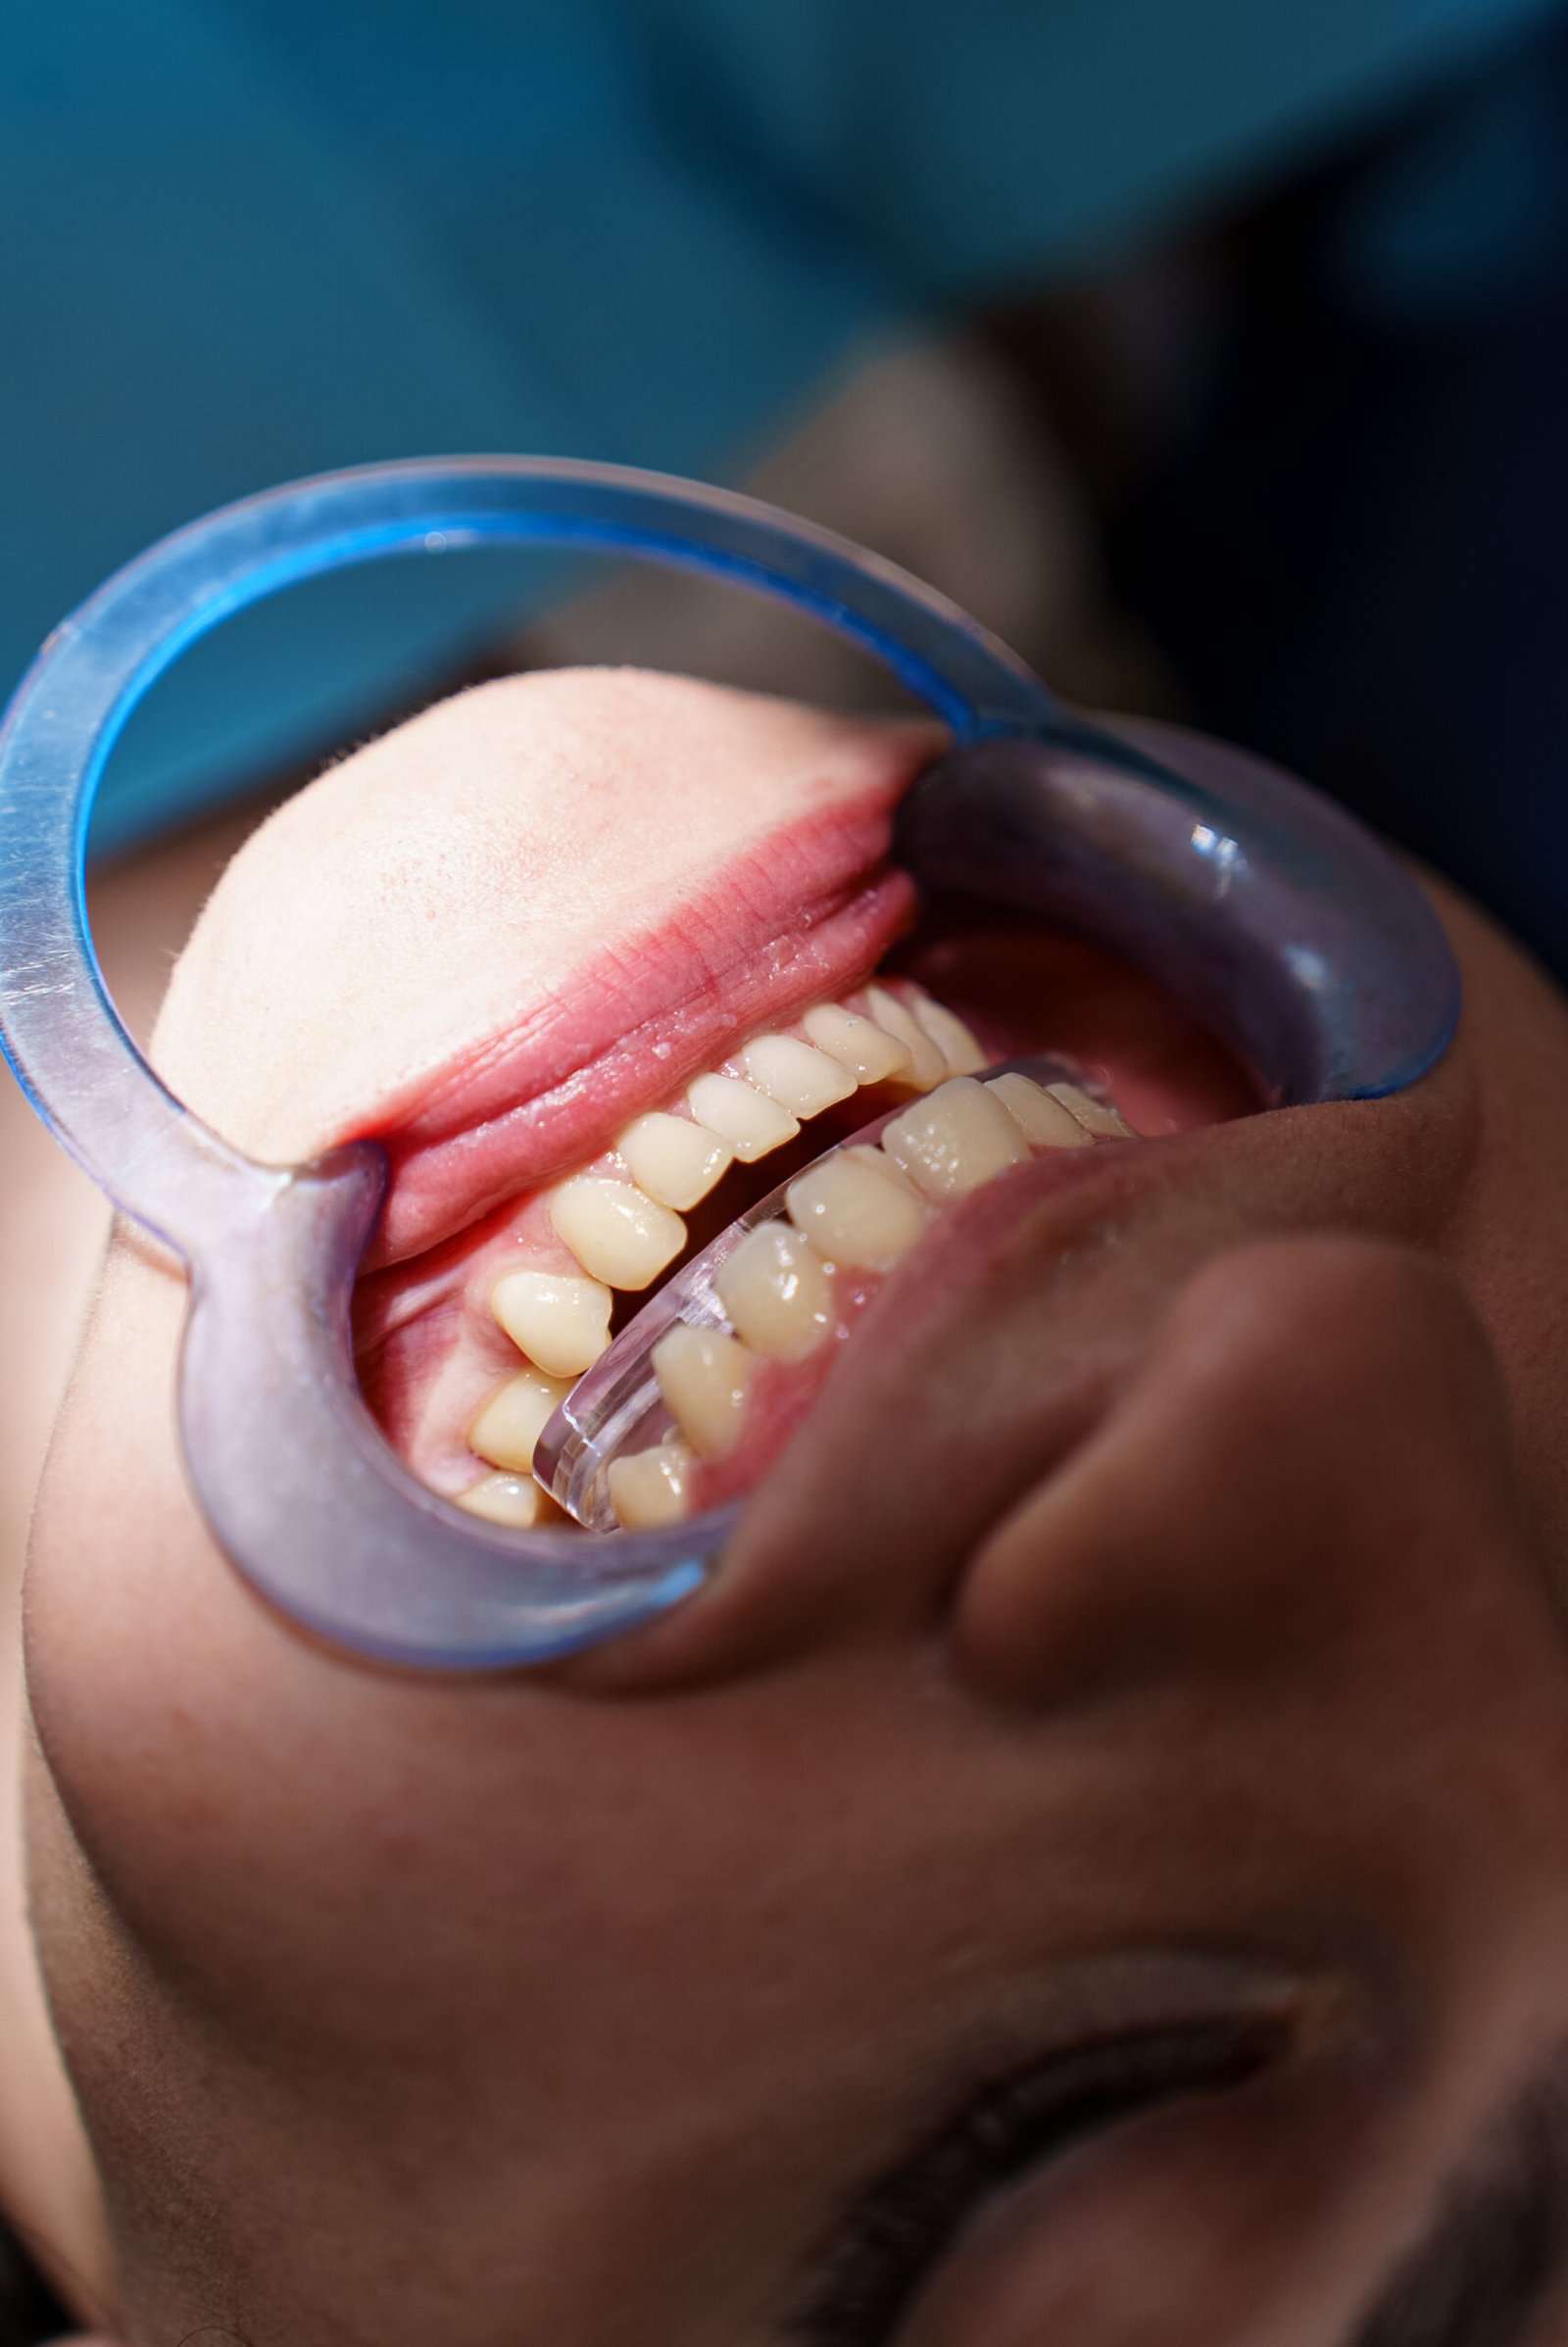

Lavori

Nuove idee

per un sorriso più sano